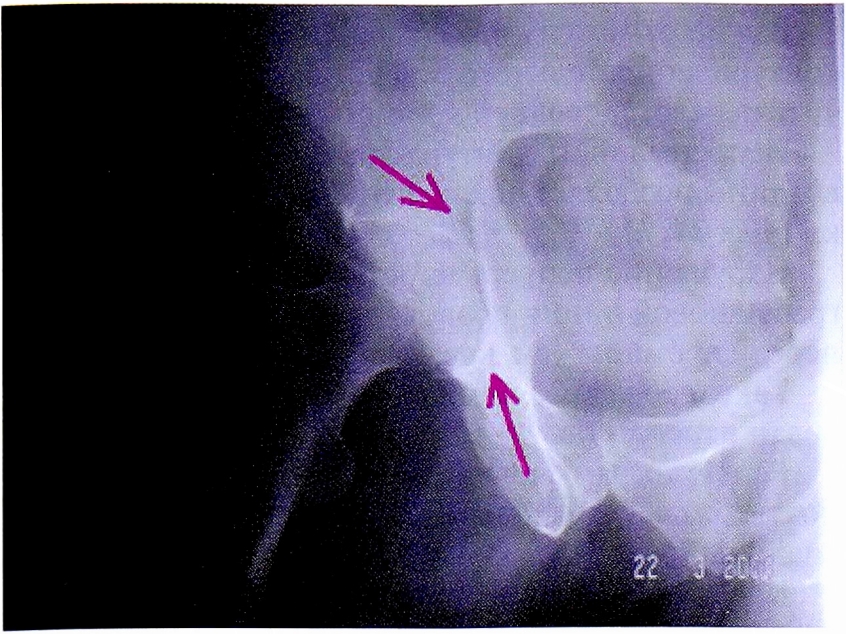

С помощью рентгенограммы в косой запирательной проекции, выполненной по методике НМИЦ ТО, диагностирован перелом задней стенки со смещением отдельного фрагмента. Также с помощью прицельного снимка определена целостность контуров запирательного отверстия (рис. 15).

Рис. 15. Рентгенография правого тазобедренного сустава в косой-запирательной проекции, выполнена по методике НМИЦ ТО. Стрелками показан перелом и отдельный фрагмент задней стенки.

Fig. 15. Obturator oblique view made with CITO method. Arrows shows separated posterior wall fragment.